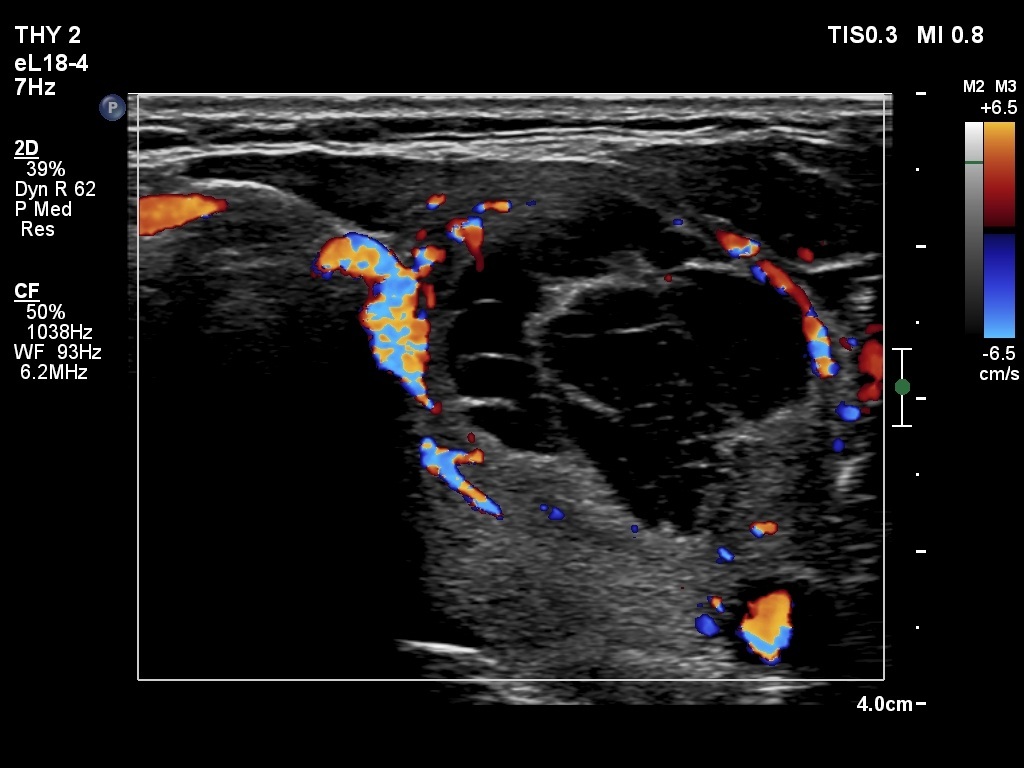

Ultrasonography. The thyroid was echonormal. The right lobe contained several discrete areas without any clinical significance. There was multi-chambered cystic nodule in the left lobe. The nodule had echonormal solid part and presented halo sign.

- The distinction between a multi-chambered cyst and a spongiform cyst is important, because in the latter the risk of malignancy is practically zero. In spongiform cysts almost the entire nodule is composed of cystic areas, and there is very small proportion of solid areas.